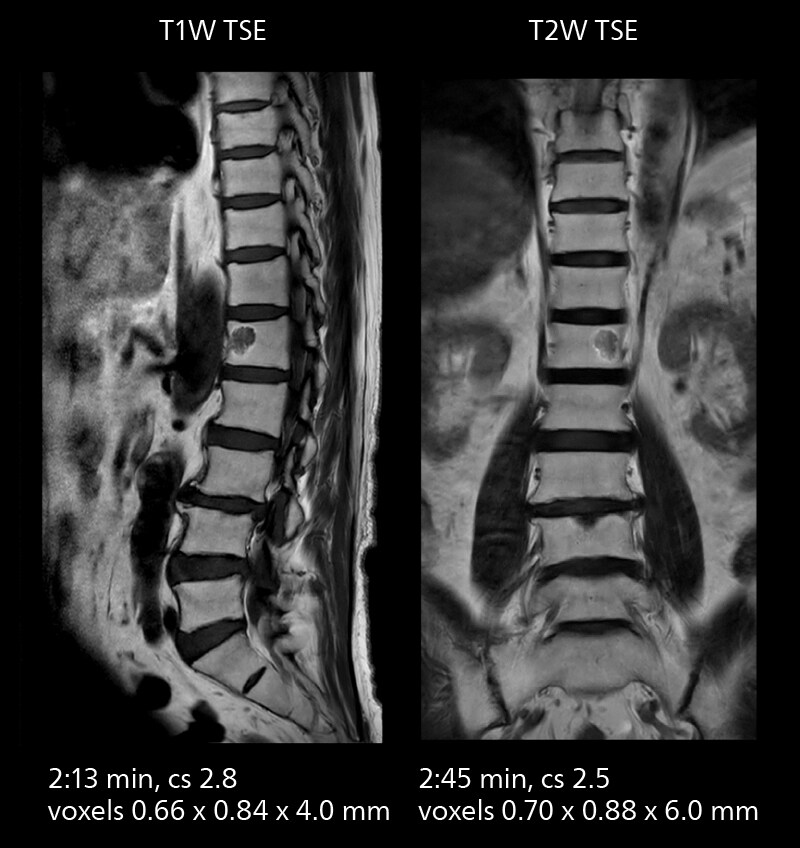

Crisp images are obtained with high resolution and short scan times using Elition X. A cyst can be seen.